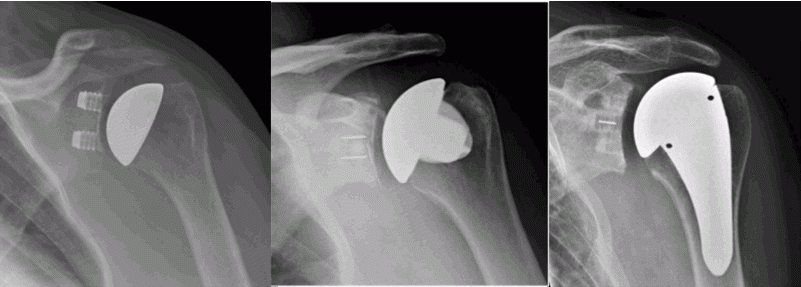

Shoulder replacements can be broadly divided into two categories – anatomic or reverse shoulder replacement.

Anatomic Shoulder Replacement

Anatomic replacements aim to preserve the shape and orientation of the joint and rely on the rotator cuff to provide control of the joint. Anatomic replacements may include total shoulder replacement where both the ball and the socket are replaced, or partial replacement (or hemiarthroplasty) where only the ball is replaced. There are many different techniques of replacing the shoulder

Humeral head resurfacing: In this procedure the head of the humerus (the ball of the joint) is resurfaced with a metal “cap”. This provides a smooth and hard bearing surface on the ball side of the joint and may be appropriate where only one side of the joint is damaged in conditions such as avascular necrosis of the humeral head. It generally provides very good pain relief if the natural socket of the shoulder is relatively healthy. The procedure conserves bone making subsequent revision surgery less challenging.

Total shoulder resurfacing: Both the ball and the socket of the joint are resurfaced in this procedure. This is a technically demanding operation and is indicated for conditions where both surfaces of the joint are damaged such as in osteoarthritis or rheumatoid arthritis. A functionally intact rotator cuff is a prerequisite. The procedure provides excellent pain relief and improvement in function. The procedure conserves bone making subsequent revision surgery less challenging.

Stemless shoulder replacement: The ball of the joint is removed and replaced with a metal prosthesis fixed in the upper part of the bone but without a stem in the shaft of the humerus. The glenoid may or may not be resurfaced at the same time.

Stemmed shoulder replacement: This is the conventional type of shoulder replacement. The ball of the joint is cut and a metal prosthesis with a stem is implanted in the humerus. If only the ball of the joint is replaced the procedure is called a Hemiarthroplasty. If the glenoid is replaced at the same time the procedure is referred to as a Total shoulder replacement.

Reverse Shoulder Replacement

In a reverse shoulder replacement the orientation of the joint is changed such that an artificial ball is fixed to the shoulder blade and a socket is fixed to the humerus. A reverse shoulder replacement is used in patients where the rotator cuff is torn or deficient.